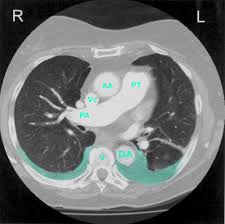

The main risk factor for pleural mesothelioma is exposure to asbestos. Advances in radiology are improving radiation therapy options for people with pleural mesothelioma. Dyspnea suggests the presence of pleural effusion, the most. Malignant pleural mesothelioma is primarily linked to asbestos exposure. Rates of pleural mesothelioma vary throughout the world and are highest in australia and the united kingdom. Treatment and diagnosis of this common symptom of mesothelioma. Pleural effusion can result from a number of conditions, such as congestive heart failure, pneumonia, cancer, liver quantification of pleural effusions: Multifocal nodules studding pleural surfaces including visceral, parietal and diaphragmatic pleura and possibly extending into radiology images.

It can cause breathlessness, chest pain and dry cough. Signs and symptoms of a pleural effusion typically herald discovery of the tumor. Mesothelioma is an important cause of lobulated or nodular pleural thickening (fig. Mesothelioma, also known as malignant mesothelioma, is an aggressive malignant tumor of the mesothelium. Pleural effusion is excess fluid around the lungs and a common symptom of mesothelioma. Patient was treated in hospital because of recurrent bilateral sanguineous pleural fluid … The main risk factor for pleural mesothelioma is exposure to asbestos. Symptomatic malignant pleural effusion is a common clinical problem. The association of history, examination, radiology and pathology is essential in the. Dyspnea suggests the presence of pleural effusion, the most. The disease occurs more often in men than women. We found pleural effusion in 23 patients. When a person is exposed to toxic levels of.